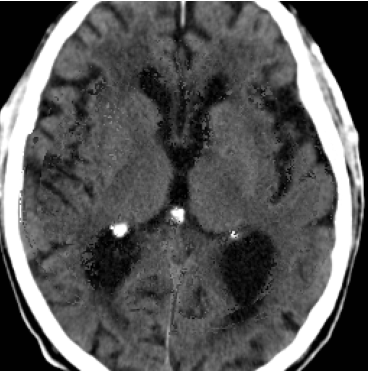

When computing with Eq. (9), the sum of the two components may not produce a perfectly coherent result. However, the incoherence is resolved by the next diffusion step, which fuses the two components better. This would not be the case if we simply computed with DDPM and then applied the mask only at the end of the sampling process. An illustration of this effect is presented in Figure 3, where we can observe how the normal image, generated by applying the mask solely at the conclusion of the sampling process (b), exhibits some artifacts and lacks a seamless transition between the edited and unedited regions.